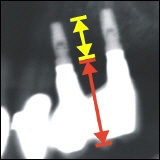

Fehlerhafte Positionierung der Implantate

Implantatverlust

Implantatbruch (Implantatfraktur)